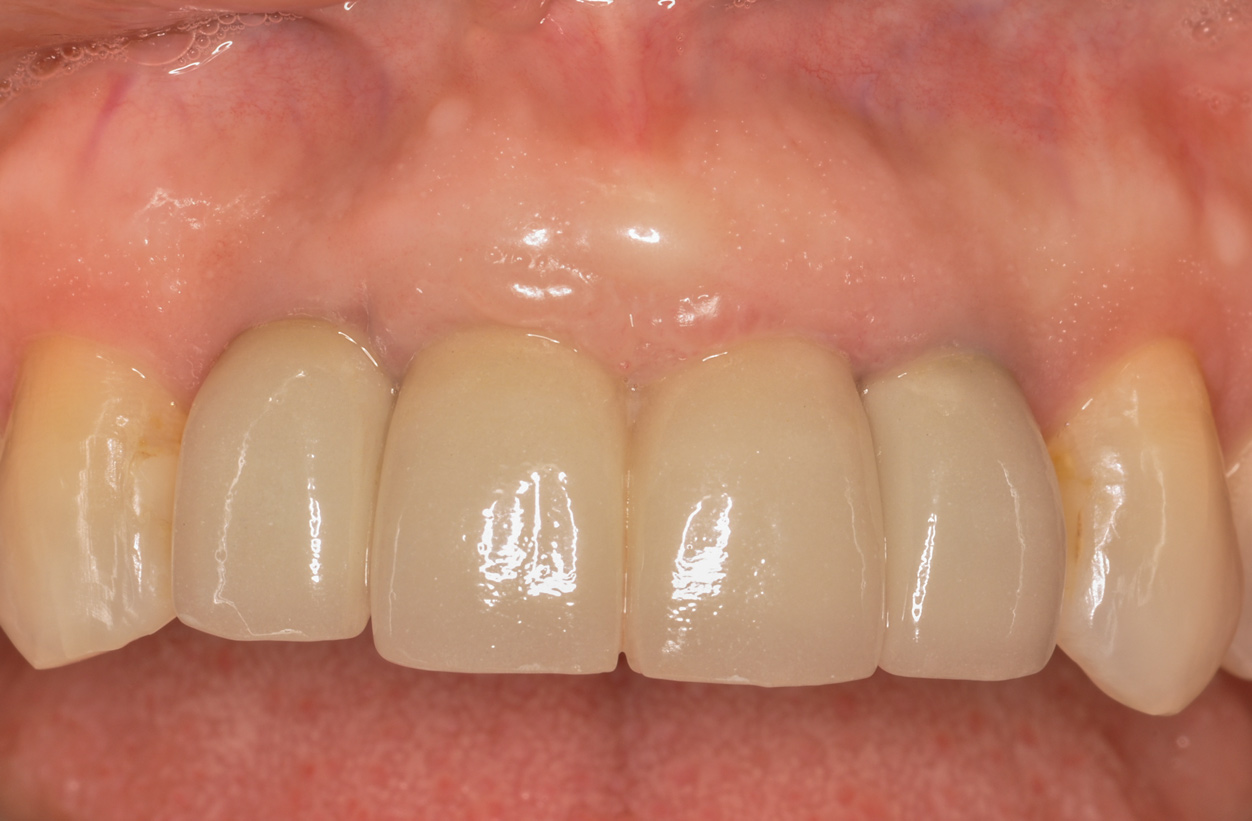

Figure 8 shows the provisionalization of No. 8 at 6 weeks postoperatively and a screw-retained provisional restoration on No. 9 to develop the subgingival transitional zone (key Nos. 8 through 10). The transitional zone will be duplicated using the custom impression coping technique. Figure 9 and Figure 10 depict the completed crowns at 5 years; implant No. 9 was screw-retained (key No. 10). In Figure 10 note the convex contours facial to implant No. 9 that are attributed to the connective tissue grafting as part of the surgical protocol creating biotype conversion from a thick to a thicker biotype. Figure 11 through Figure 13 show 5-year postoperative patient smile, periapical x-ray, and CBCT, respectively.

Fig 9. Completed crowns at 5 years, front view. Implant No. 9 was screw-retained (periodontist: Robert A. Levine, DDS; restorative dentist: Zola Makrauer, DMD).

Figure 9

Fig 10. Completed crowns at 5 years, angled view. Note the convex contours facial to implant No. 9 attributed to the connective tissue grafting.

Figure 10